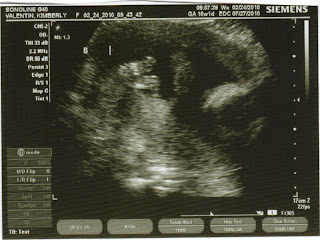

Imagine my amazement when I got my latest ultrasound and was told by the Ultrasound Tech, Leslie, that I am indeed having TWO boys! For those of you who have seen my nursery closet and the numerous girls dresses and clothes I have collected, can only imagine the panic I felt knowing I have NO boys clothes. Luckily I decorated the nursery gender neutral. In any case, it gave me the opportunity to do a little shopping. ;0)

In all honesty I was only disappointed for about 3 seconds! Jorge and I left the office with the biggest smiles on our faces. He felt the same way I did. That will give him a total of 4 boys! Lord help me! Two little Jorge's running around. The truth of the matter is I couldn't be happier. Both babies are healthy and growing like crazy and that's all that matters. My belly is so big already and I'm sure that isn't going to stop any time soon. I am in my 5th month (19 weeks) and still haven't felt them kick. Not rushing it as I'm sure there will be 4 little feet in my ribs for many months to come.

I almost forget, names. We have chosen Samuel and Isaiah. I guess the Lord was saving my marriage by giving me two boys since we couldn't decide on a girls name. I have posted a pic of Isaiah's little feet and tooshy! So sweet.